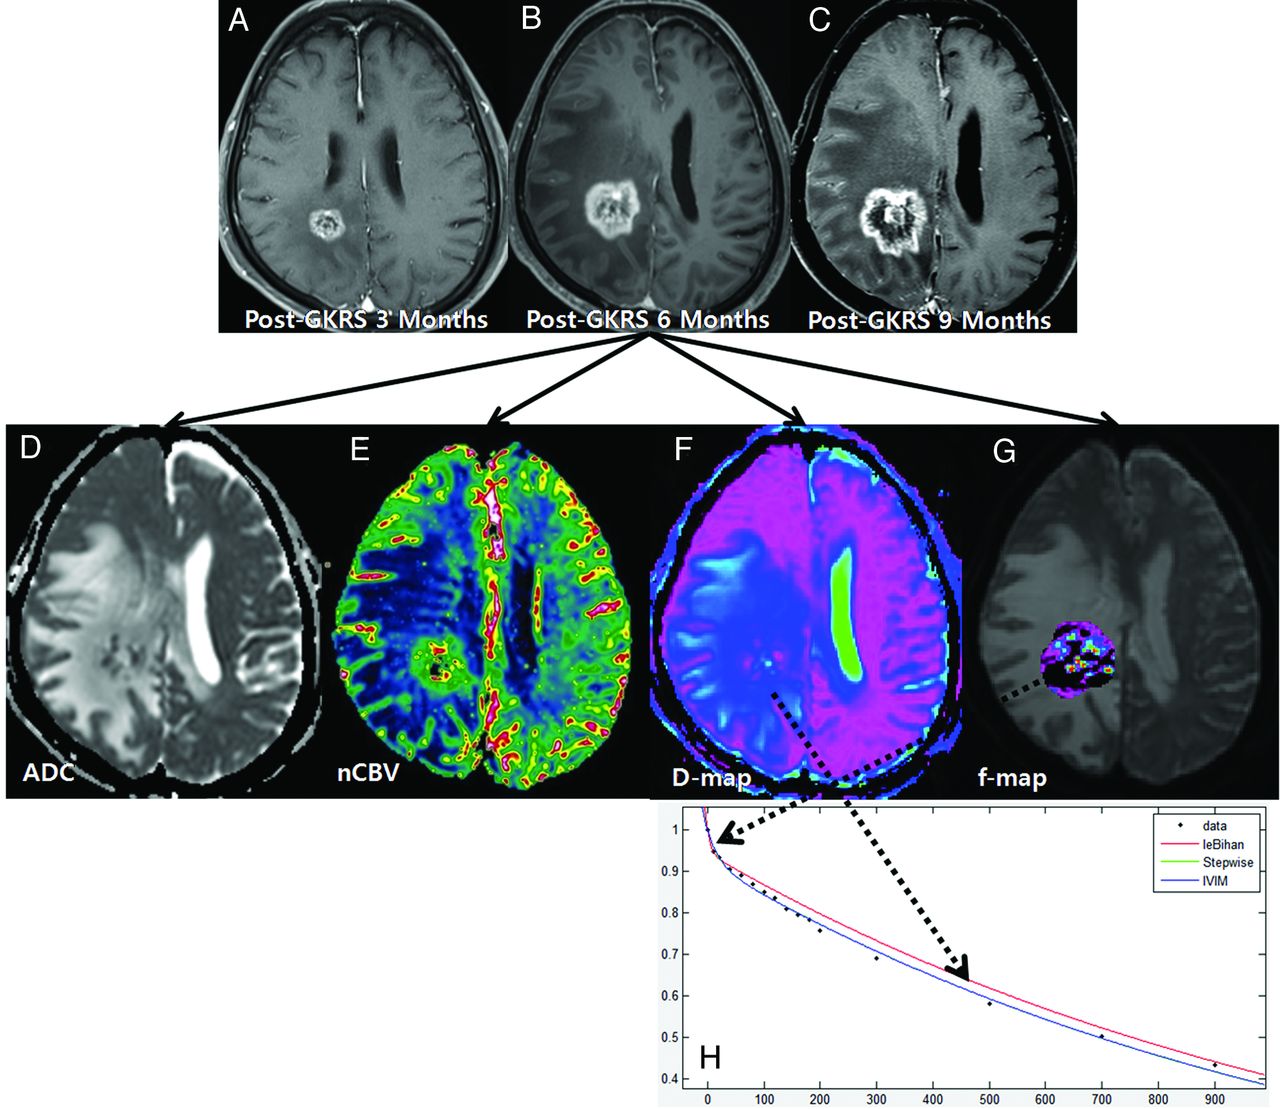

Among the 91 study patients, analysis of all of the patients with recurrent tumor and 9 patients with treatment effect showed that the signal decay curve, plotted as a function of the diffusion b-values, was biexponential and ranged from 0 to 900 s/mm2. The recurrent tumor group showed more rapid signal decay than the treatment effect group in the range of lower b-values (b < 200 s/mm2) (Fig 3). In the remaining 43 patients with treatment effect, the signal decay curve was similar to the monoexponential pattern (Fig 2). The f, nCBV, D, and ADC maps of representative cases of recurrent tumor and treatment effect are shown in Figs 2 and 3.

A 54-year-old man with recurrent tumor following GKRS. Axial contrast-enhanced T1-weighted images, obtained 3 (A), 6 (B), and 9 months (C) after GKRS, show a progressively enlarging necrotic contrast-enhancing lesion in the right parietal lobe. The ADC (D) and nCBV (E) maps show a visual decrease of the ADC and a visual increase of the nCBV in the corresponding area of the contrast-enhancing lesion in B, respectively. The D (F) and f (G) maps show a visual decrease of the D value and a visual increase of the f value in the corresponding area of the contrast-enhancing lesion in B, respectively. H, The signal-decay curve, plotted as a function of the diffusion b-values, is biexponential.